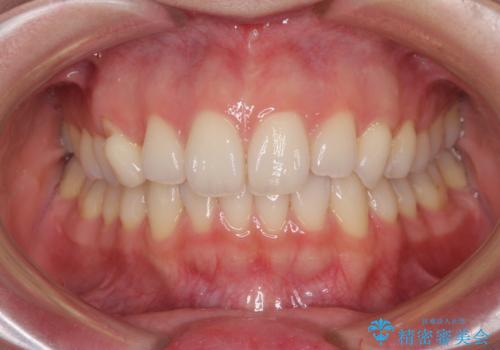

- 前歯のクロスバイトや残存している乳歯を気にして来院された患者様です。

上顎骨の幅が下顎骨よりも小さいので、拡大装置により骨幅を広げて上下関係を改善し、その後インビザラインにて歯並びを整えることとしました。

上下の骨幅を改善したことで、スムーズに歯列矯正を行うことができました。